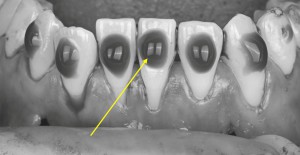

※歯間部の診査

歯と歯の間の歯ぐきや骨の支えの状態について、専用の器具(プローブ)を用いて測定・確認を行います。

その結果をもとに、歯ぐきの回復を目的とした治療(根面被覆)が適しているかどうかを、総合的に判断します。

診断

下顎両側中切歯 Cairoの分類RT2

下顎右側側切歯、下顎左側犬歯Cairoの分類RT1